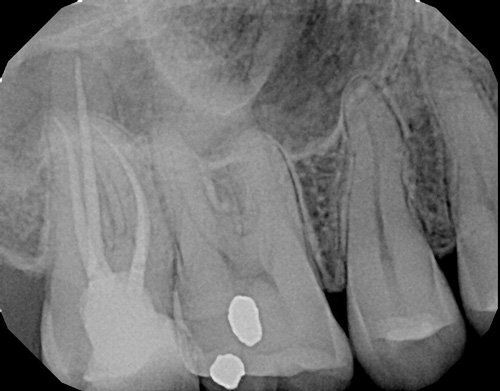

Patient needed multiple restorations, decay removed from upper teeth, crowns placed from canine to canine. Patient Missing 1st lower molar, implant and crown placed, chewing function restored. 2nd molar cracked, causing severe pain, nerve removed from tooth with root canal therapy